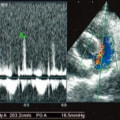

D:超音波写真 狭窄部の異常血流速度の測定

1年ほど前より左側胸壁からLevine 3/6の心雑音が聴取されていた。雑音の精査のため、心エコー検査を行ったところ、左室流出路の狭窄を伴う肥大型心筋症(閉塞型肥大型心筋症)と判明した。心室の拡張性を上げるため、βブロッカーであるカルベジロールを用いた治療を行っている。肥大型心筋症は犬の心疾患のように、心拡大を認めないことも多く、レントゲン写真のみで心疾患の有無を判断する事が出来ない。また、閉塞を伴わない肥大型心筋症と異なり、閉塞型の本疾患の治療に対し、Caチャネルブロッカーは推奨されない。